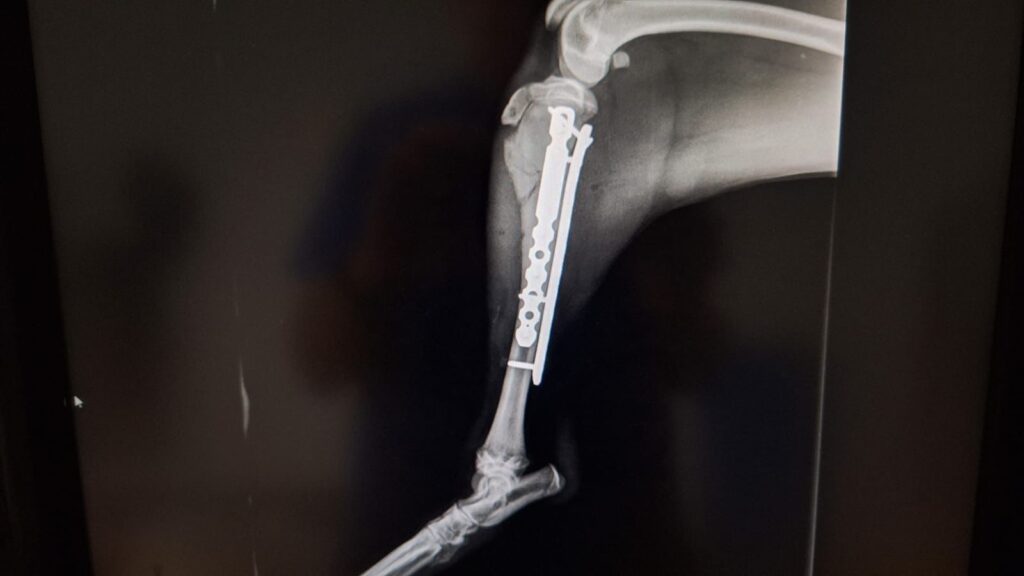

Kaiser braucht eure Hilfe

Kaiser wurde in Spanien überfahren und hat massive Verletzungen an 3 Beinen erlitten. Er wurde operiert und hat sich inzwischen auch schon recht gut erholt. Kaiser ist erst 9 Monate und ein sehr lieber und geduldiger Junge.

Natürlich sind durch die OP wieder hohe Tierarztkosten angefallen – auch hier sind wir wie immer sehr dankbar über jeden Euro, der uns unterstützend erreicht – Betreff: Kaiser.